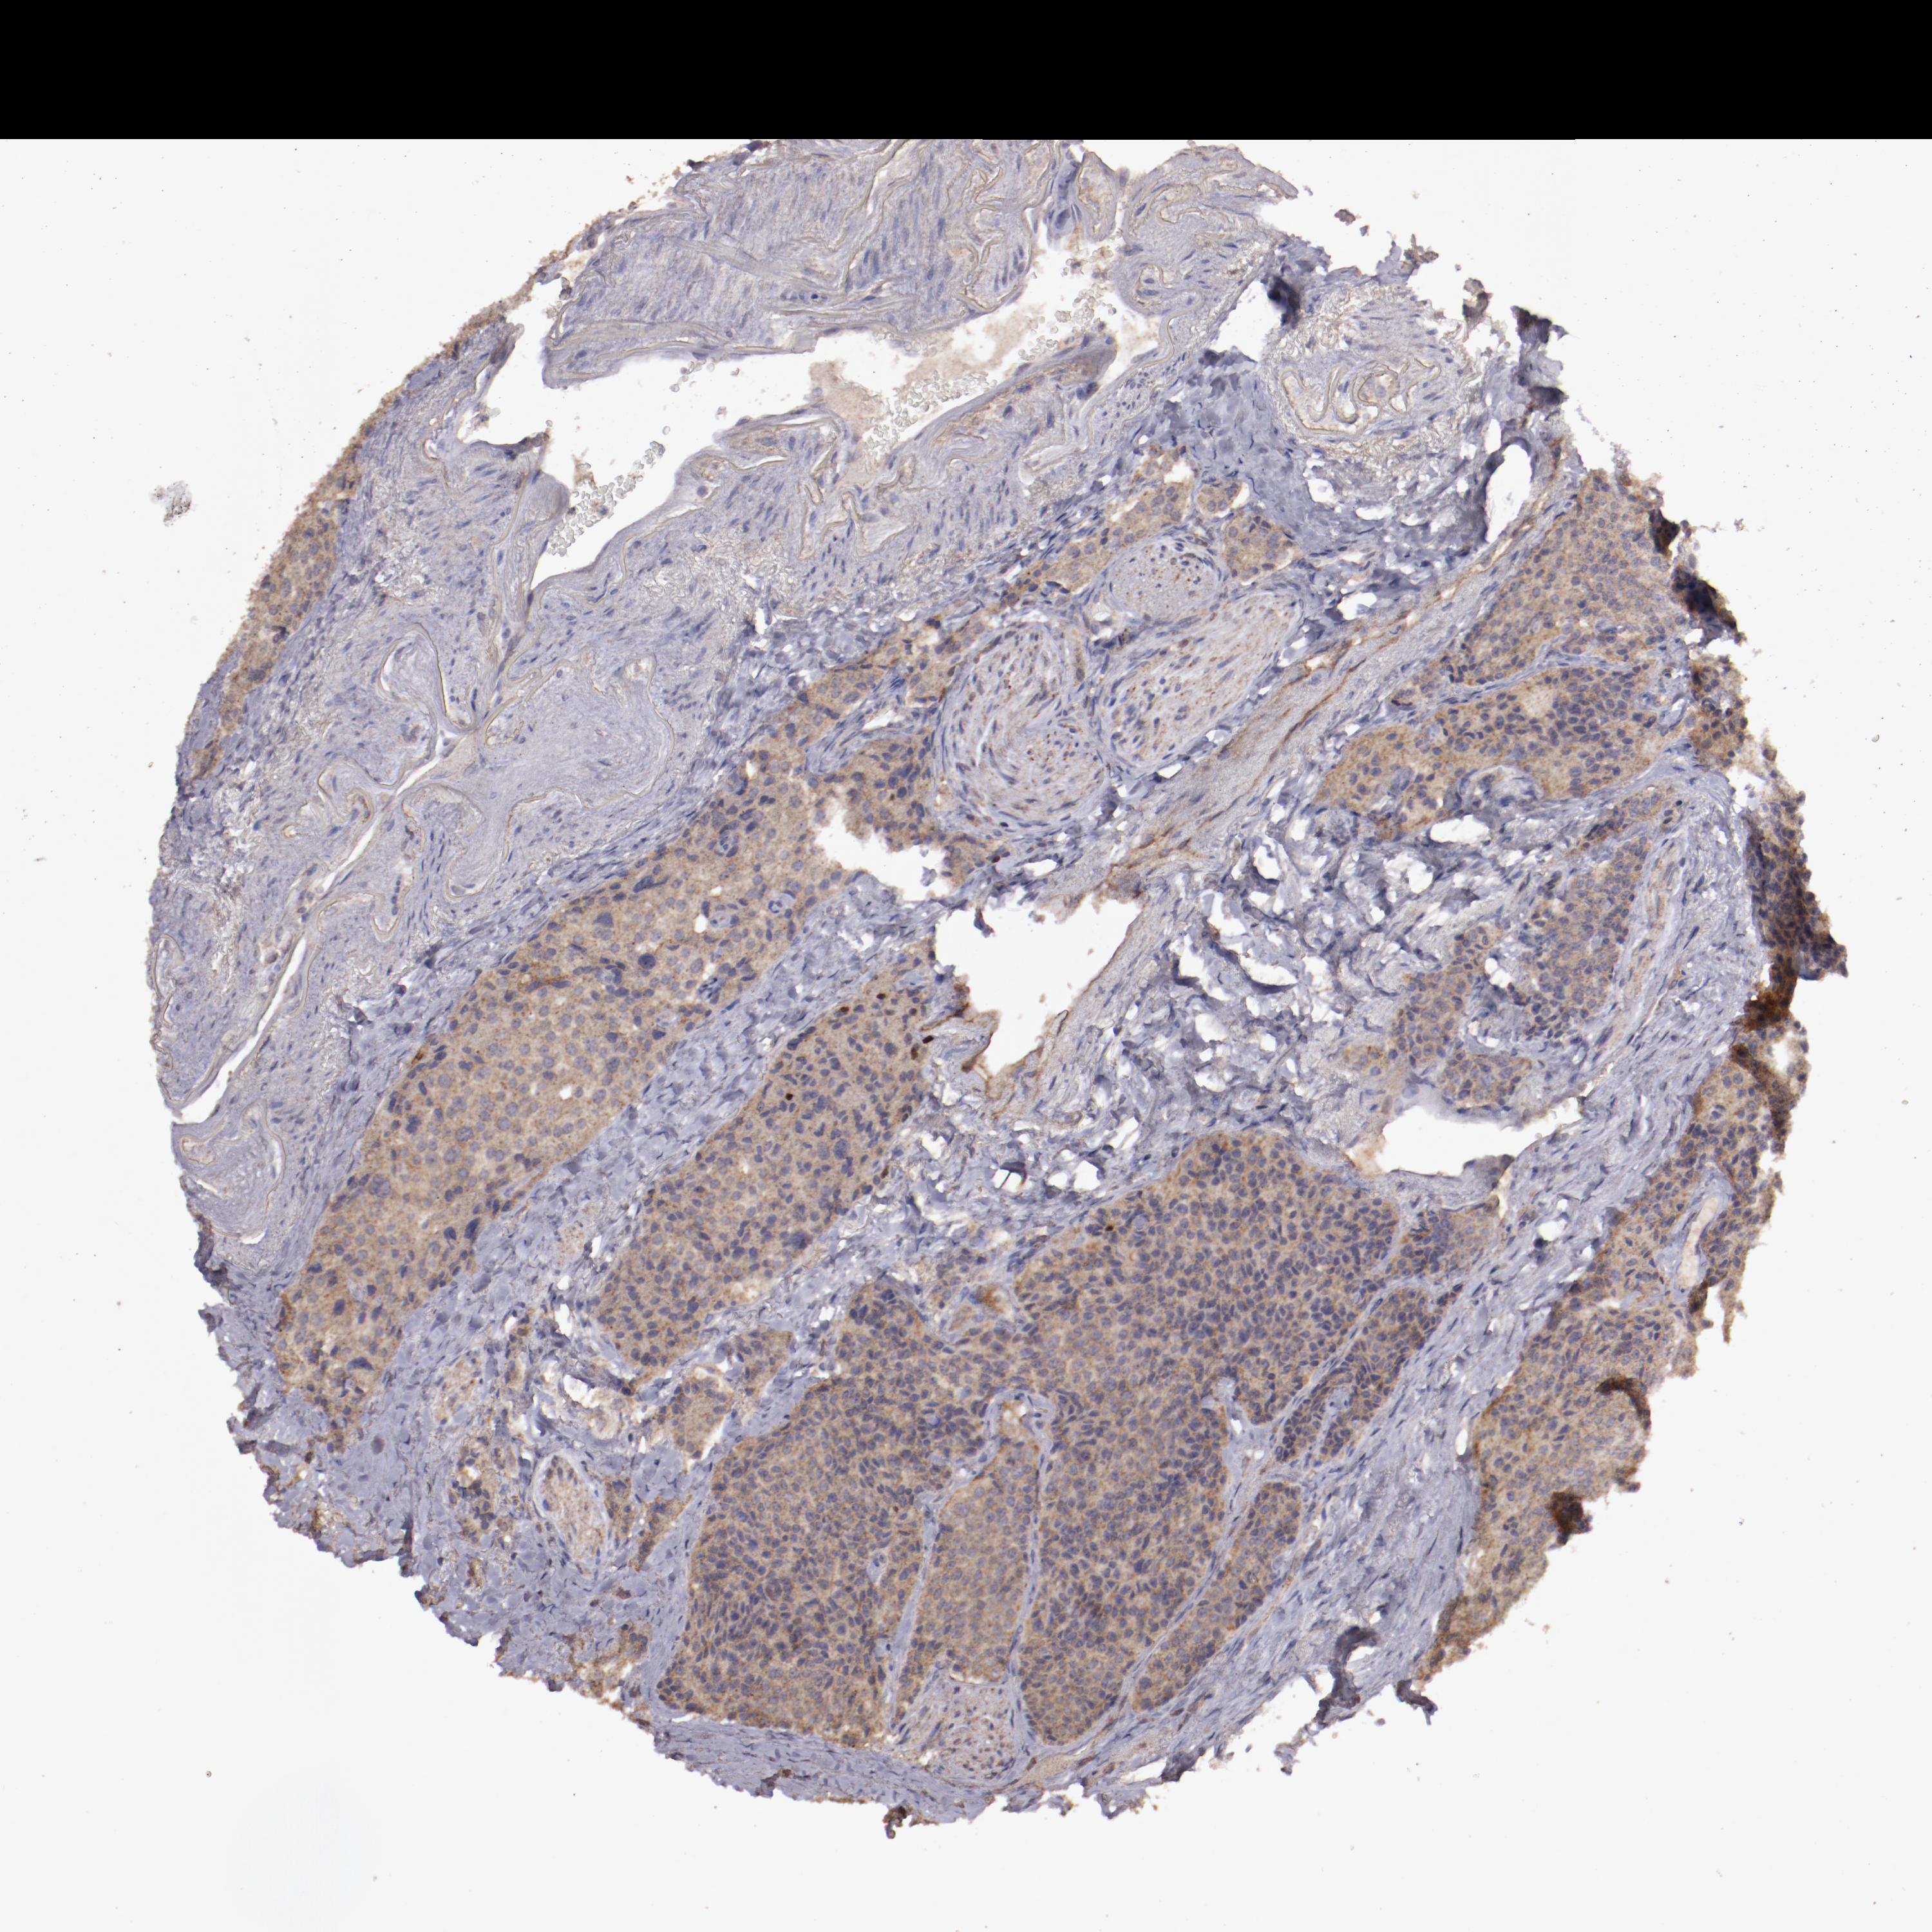

CARCINOID - Protein expressioni

A mouse-over function shows sample information and annotation data. Click on an image to view it in a full screen mode. Samples can be filtered based on level of antibody staining by selecting one or several of the following categories: high, medium, low and not detected. The assay and annotation is described here.

Antibody stainingi

Antibody staining in the annotated cell types in the current human tissue is reported as not detected, low, medium, or high, based on conventional immunohistochemistry profiling in selected tissues. This score is based on the combination of the staining intensity and fraction of stained cells.

Each image is clickable and will lead to virtual microscopy that enables deeper exploration of all samples and also displays staining intensity scores, fraction scores and subcellular localization as well as patient and tissue information for each sample.

Antibody HPA001869

Antibody HPA023882

Staining

High

Medium

Low

Not detected

Intensity

Strong

Moderate

Weak

Negative

Quantity

>75%

75%-25%

<25%

None

Location

Nuclear

Cytoplasmic/membranous

Cytoplasmic/membranous,nuclear

Carcinoid, malignant, NOS

Carcinoma, NOS